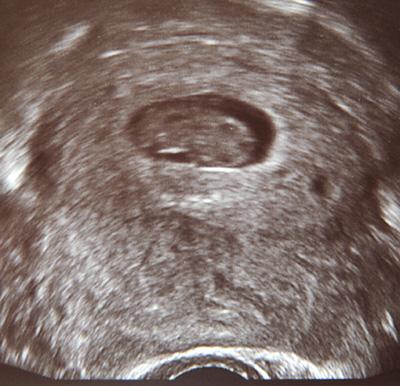

Es ist alles sowas von i.O.!*freufreufreu* Das kleine Herzchen hat geblubbert und Fröschlein ist 2,27cm groß. Laut meiner Fä wäre das schon 9+0,nee kann aber nicht sein. In der Biometrietabelle von Dr.Bluni bin ich 8+4 so wie´s sein soll.Passt also alles toll. Ach Mädels, ich bin sowas von froh, dass alles gut ist. Evs wie war dein Termin? LG,Anja

Achso,hier noch ein Bildchen.Auch nur abfotografiert.Rechts ist das Köpfchen..halt ein bisschen zusammengekuschelt.:)